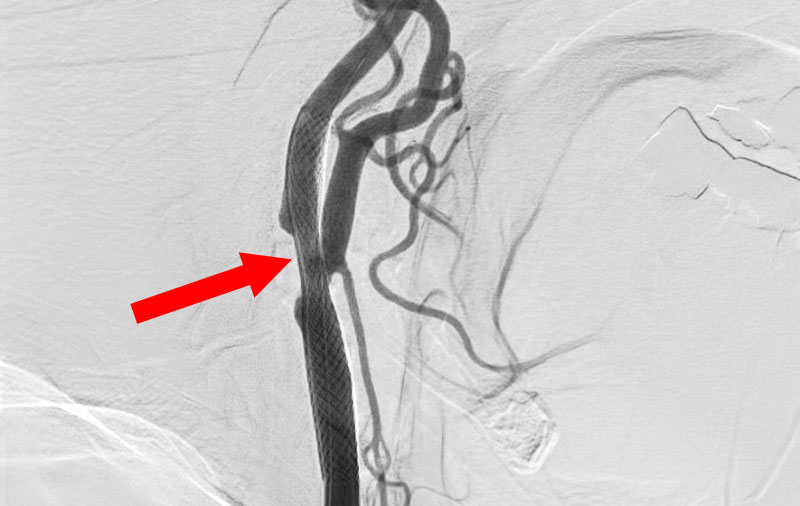

No.1590 手術前

No.1590 手術中

No.1590 手術後